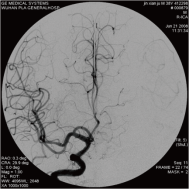

颈内动脉创伤性假性动脉瘤覆膜支架治疗前后(三维像是术前) 右侧颈内动脉后交通动脉瘤栓塞术后完全闭塞

弹簧圈栓塞后造影示左椎动脉夹层动脉瘤消失, 左椎动脉、 多发动脉瘤夹闭术前、术中

左侧小脑后下动脉循环通畅